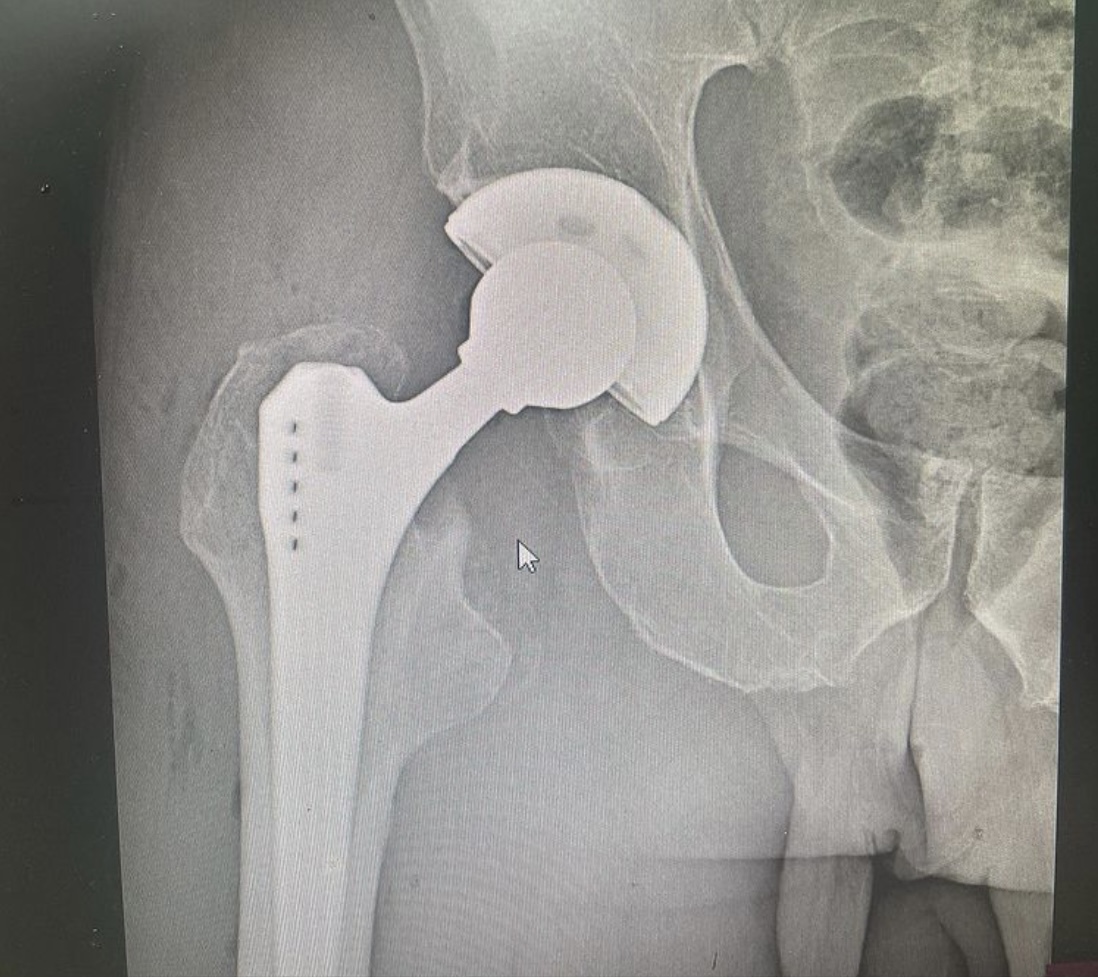

Во втором случае - пациент 84 года с переломом шейки бедренной кости. Выполнено тотальное эндопротезирование тазобедренного сустава эндопротезом цементной фиксации.

В обоих случаях пациент активизируется на следующий день после операции. Со второго дня разрешена ходьба с полной нагрузкой на оперированную конечность.